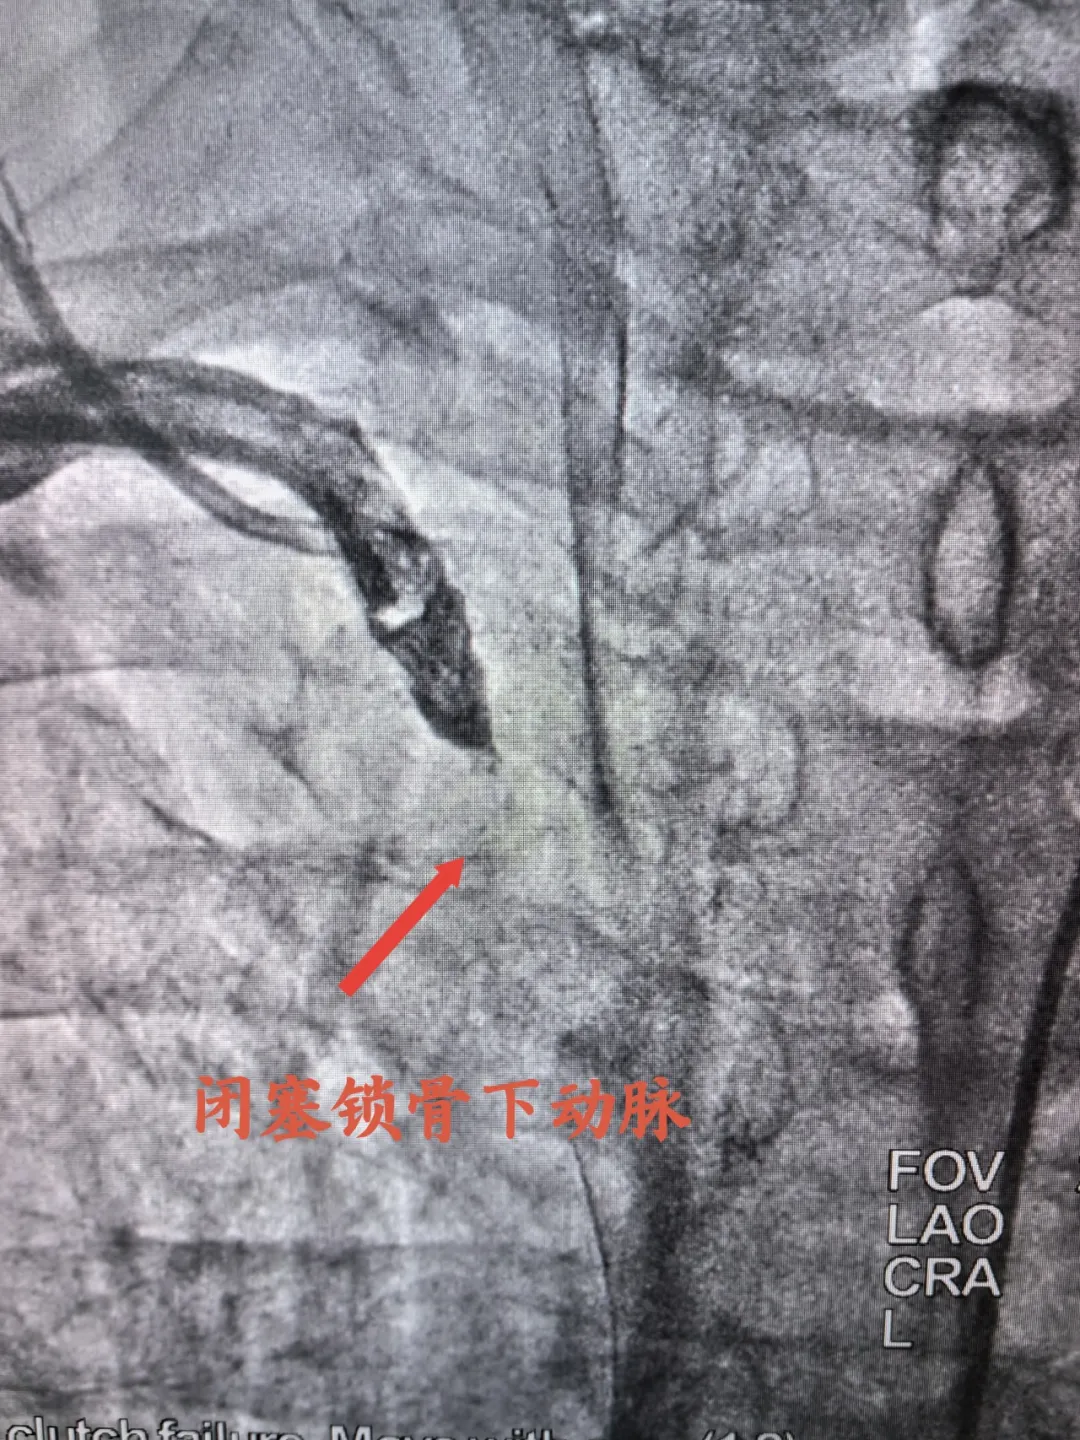

入院完善各項檢查后考慮為冠心病合并右鎖骨下動脈狹窄可能,經(jīng)宋坤青主任團隊研究后,決定為該患者施行冠脈造影+鎖骨下動脈造影。經(jīng)過嚴謹?shù)男g(shù)前討論及充分的術(shù)前準備后,在2024年06月07日上午,宋坤青主任、趙博韜副主任及楊亞楠、冉德聰主治醫(yī)師為該患者進行了造影手術(shù),結(jié)果提示右冠狀動脈近近段90%狹窄,前降支近中段90%狹窄,右側(cè)鎖骨下動脈閉塞。

閉塞鎖骨下動脈